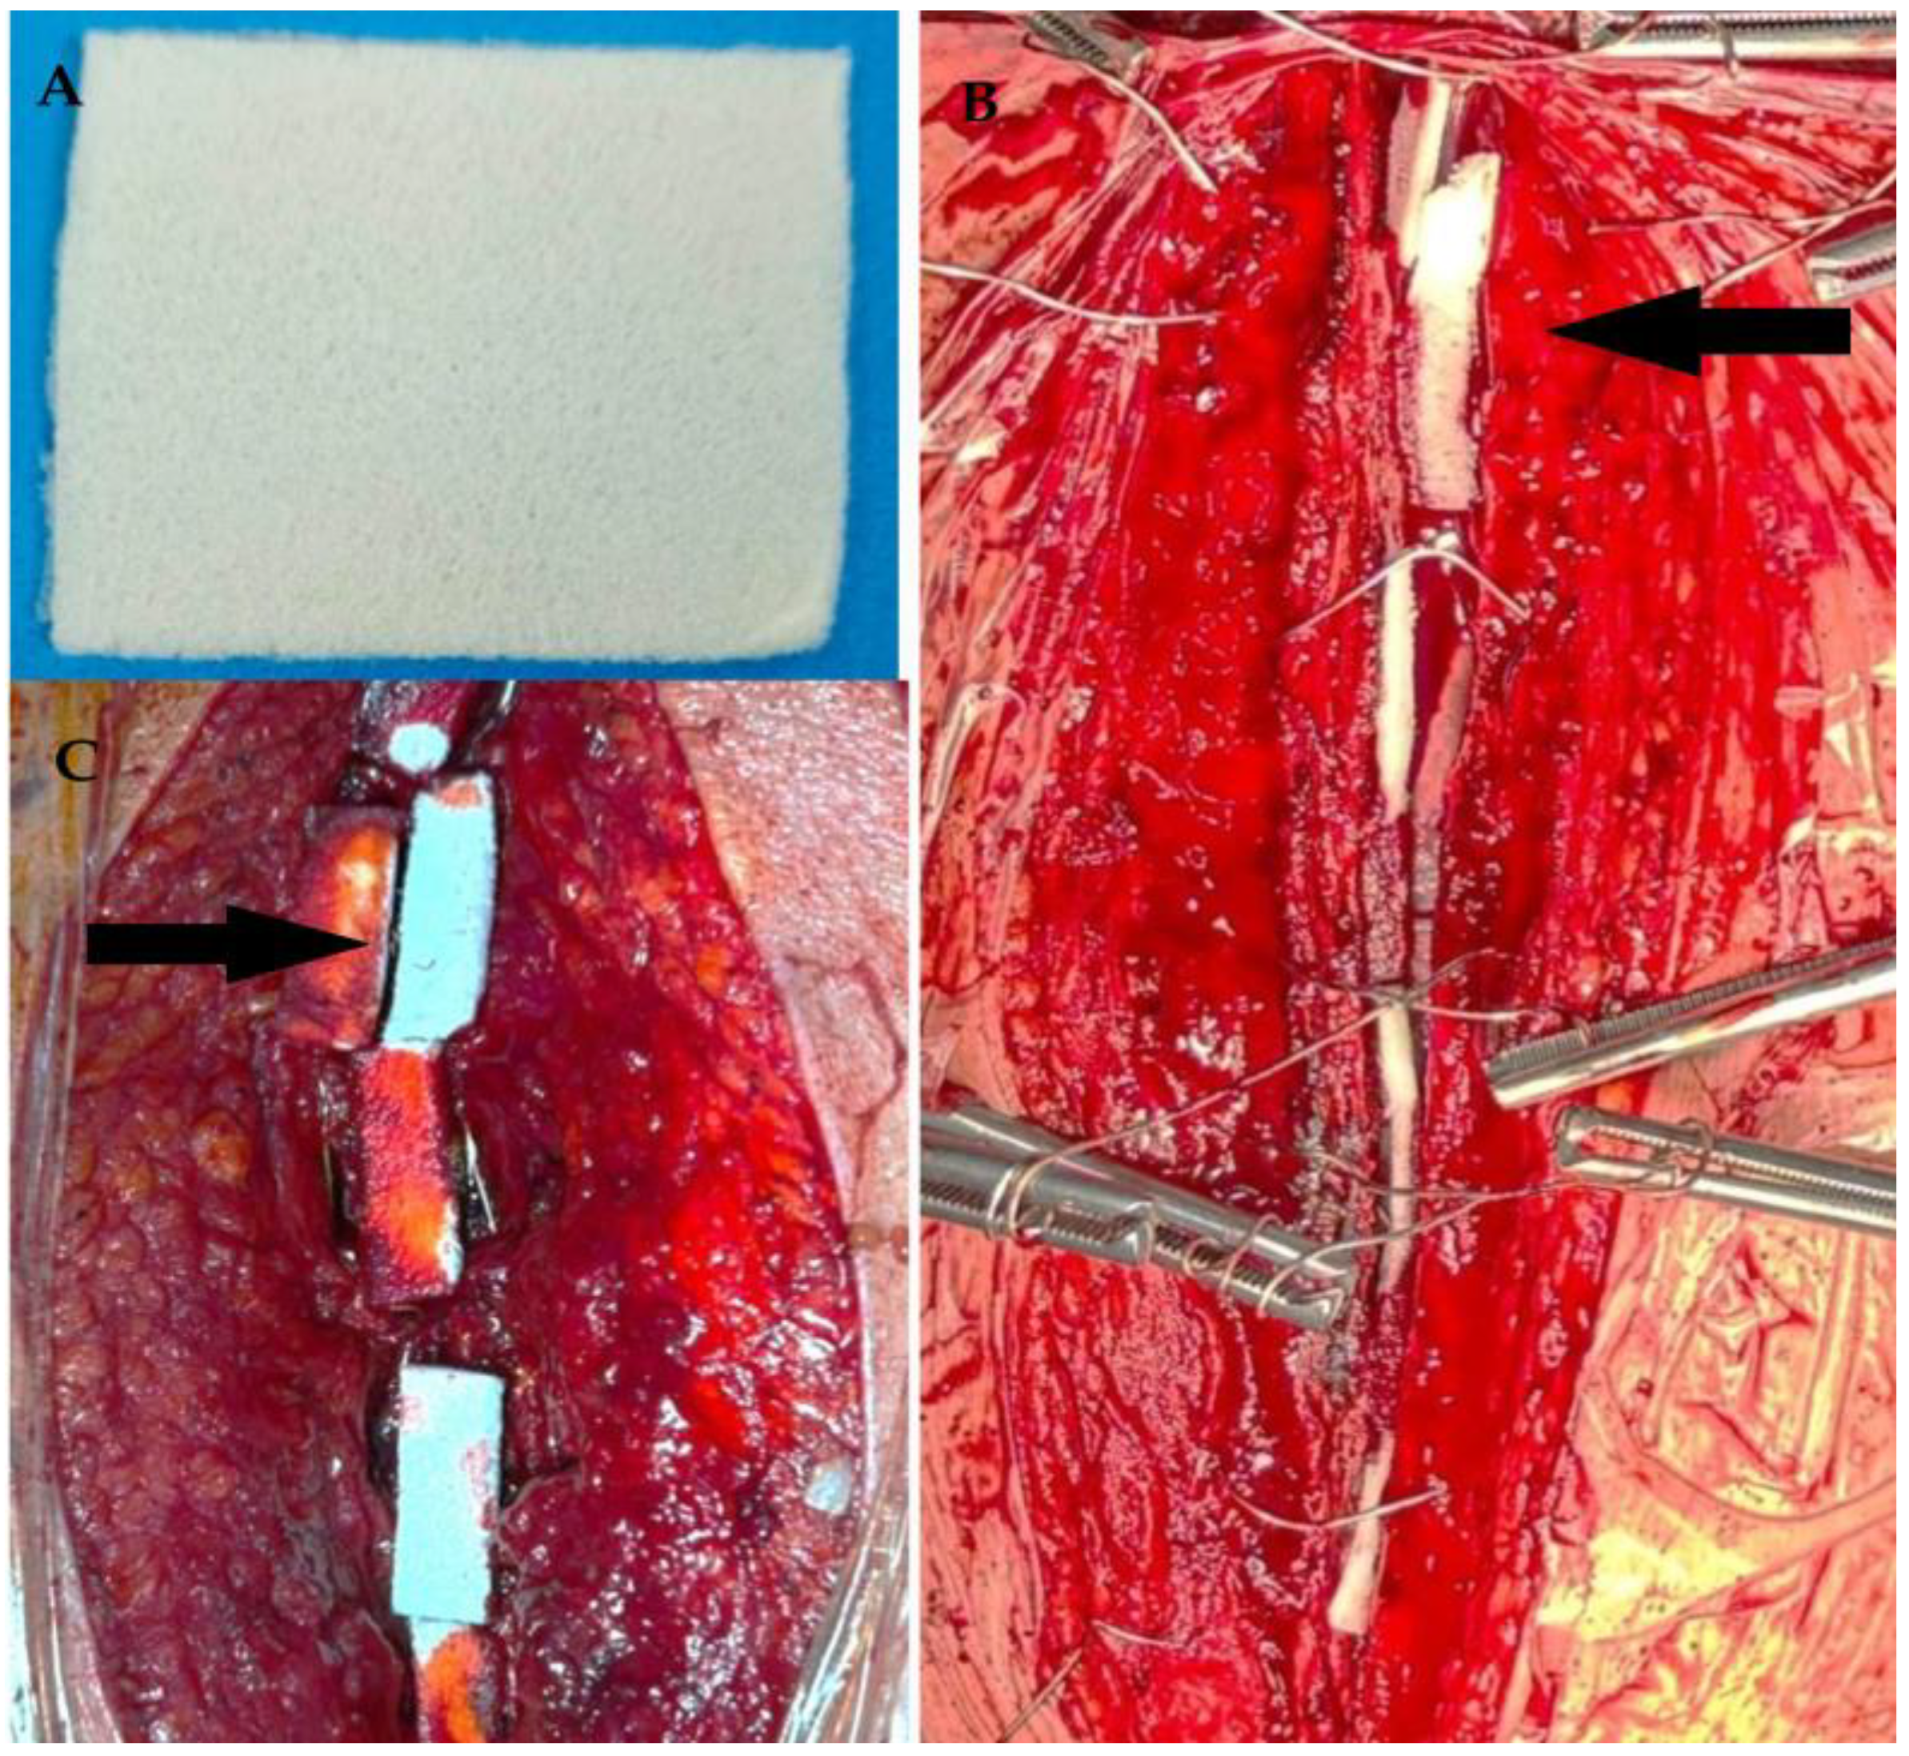

2.4. Surgical Technique